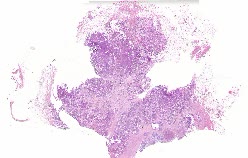

10517 |

左乳肿块 |

女, 52岁, 体检发现乳房结节,已婚已育,已绝经,否认家族遗传病史。否认家... |

上海市第一人民医院 |

有诊断 |